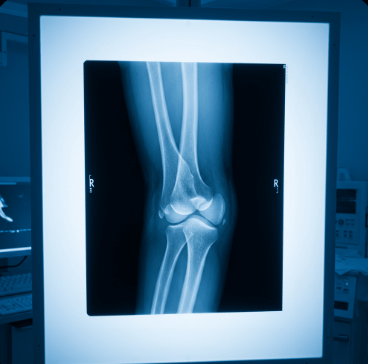

진료과 선택 팁: 정형외과에서 X-ray나 초음파 검사를 받을 수 있고, 만성 통증은 재활의학과나 한의원에서도 치료 가능합니다.

Q7. 팔꿈치 골절은 어떻게 치료하나요?

A. 골절 정도에 따라 깁스 고정이나 수술이 필요하며, 회복 기간은 6-12주 정도입니다.